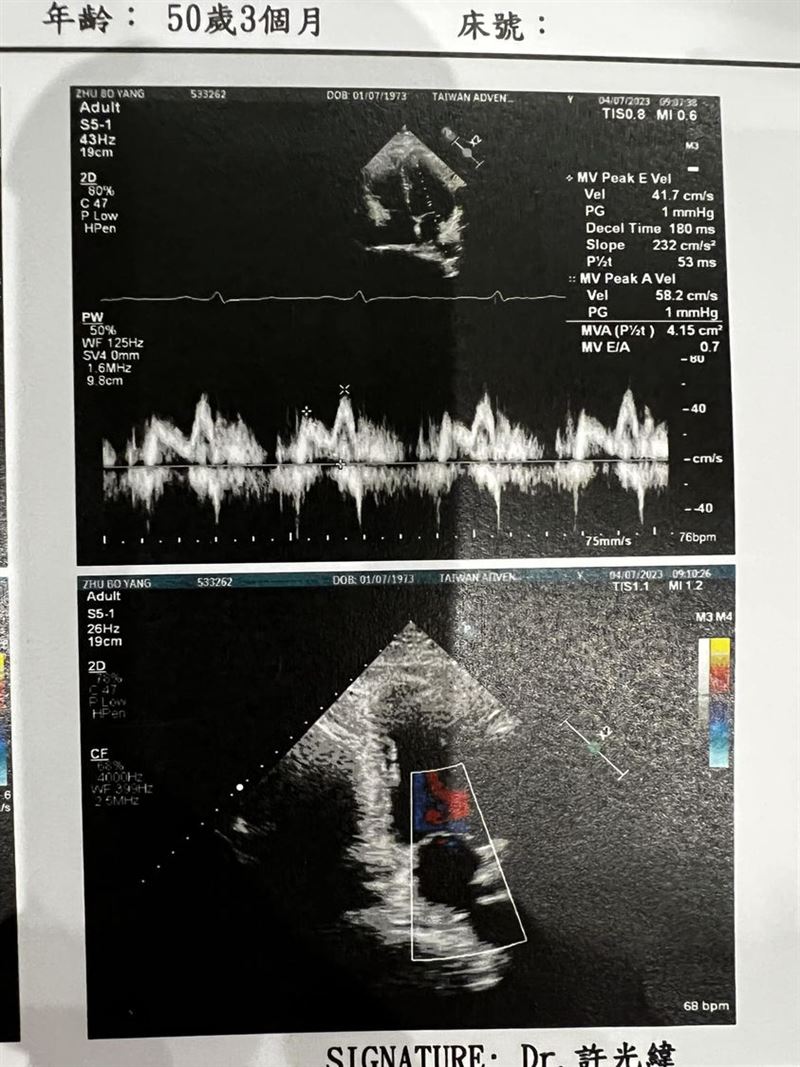

▲Paul檢查出4.6公分心臟主動脈瘤。(圖/翻攝自臉書)

50歲藝人Paul(朱柏仰)先前上節目時,被一位來賓提醒最好去做一次精密檢查,而他也決定聽從建議;沒想到,竟真的被查出心臟有4.6公分主動脈瘤,且天生只有兩片心臟瓣膜,這樣的情況與劉真相同,之後需要進行追蹤檢查。

誰料,檢查報告都還沒出來,醫院就先忍不住先通知,表示他有一顆4.6公分的主動脈瘤,且正常人有三片心臟瓣膜,但他卻先天少一片,跟劉真一樣的心臟疾病。

Paul表示,由於主動脈瘤位於升主動脈,無法以微創手術來放置支架,需要進行傳統手術;如若進行了傳統手術,最好連瓣膜修復一起做。考慮到手術的困難性與複雜性,醫生建議他在主動脈瘤未超過5公分、兩心室壓力差還不大的情況下,暫時先以每半年定期追蹤為主,手術等之後再考慮。